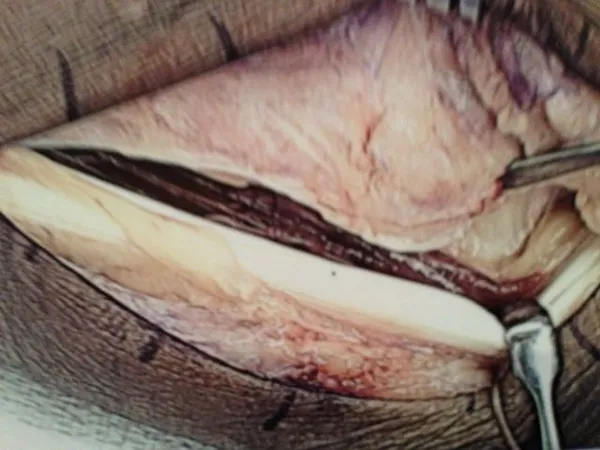

Removal of Torn portion and debulking of tendon. (below)

Final Placement of Peroneal Tendons back in the fibular groove and suture replacement for repair of Superior Peroneal Retinaculum and Tendon Sheath. (below)